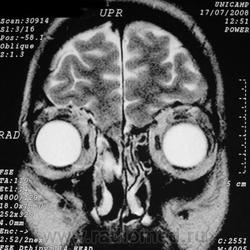

Фронтоэтмоидальное энцефалоцеле.

Отдел патологии, школа медицинских наук.

Государственного Университета Кампинас (UNICAMP).

Кампинас, Сан-Паулу, Бразилия.

Цефалоцеле